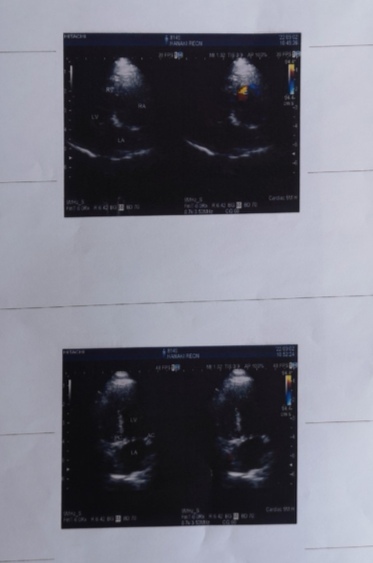

【僧帽弁閉鎖不全症】

その病院では【僧帽弁形成術】という非常に高度な術式を用います。

「心臓僧帽弁閉鎖不全症」

『この病気は大きな苦しみを伴う病気で死と隣り合わせの病気だが、

手術の成功率は95%以上あり、術後の合併症を乗り越えれば、幸せな日々を取り戻せる病気である』